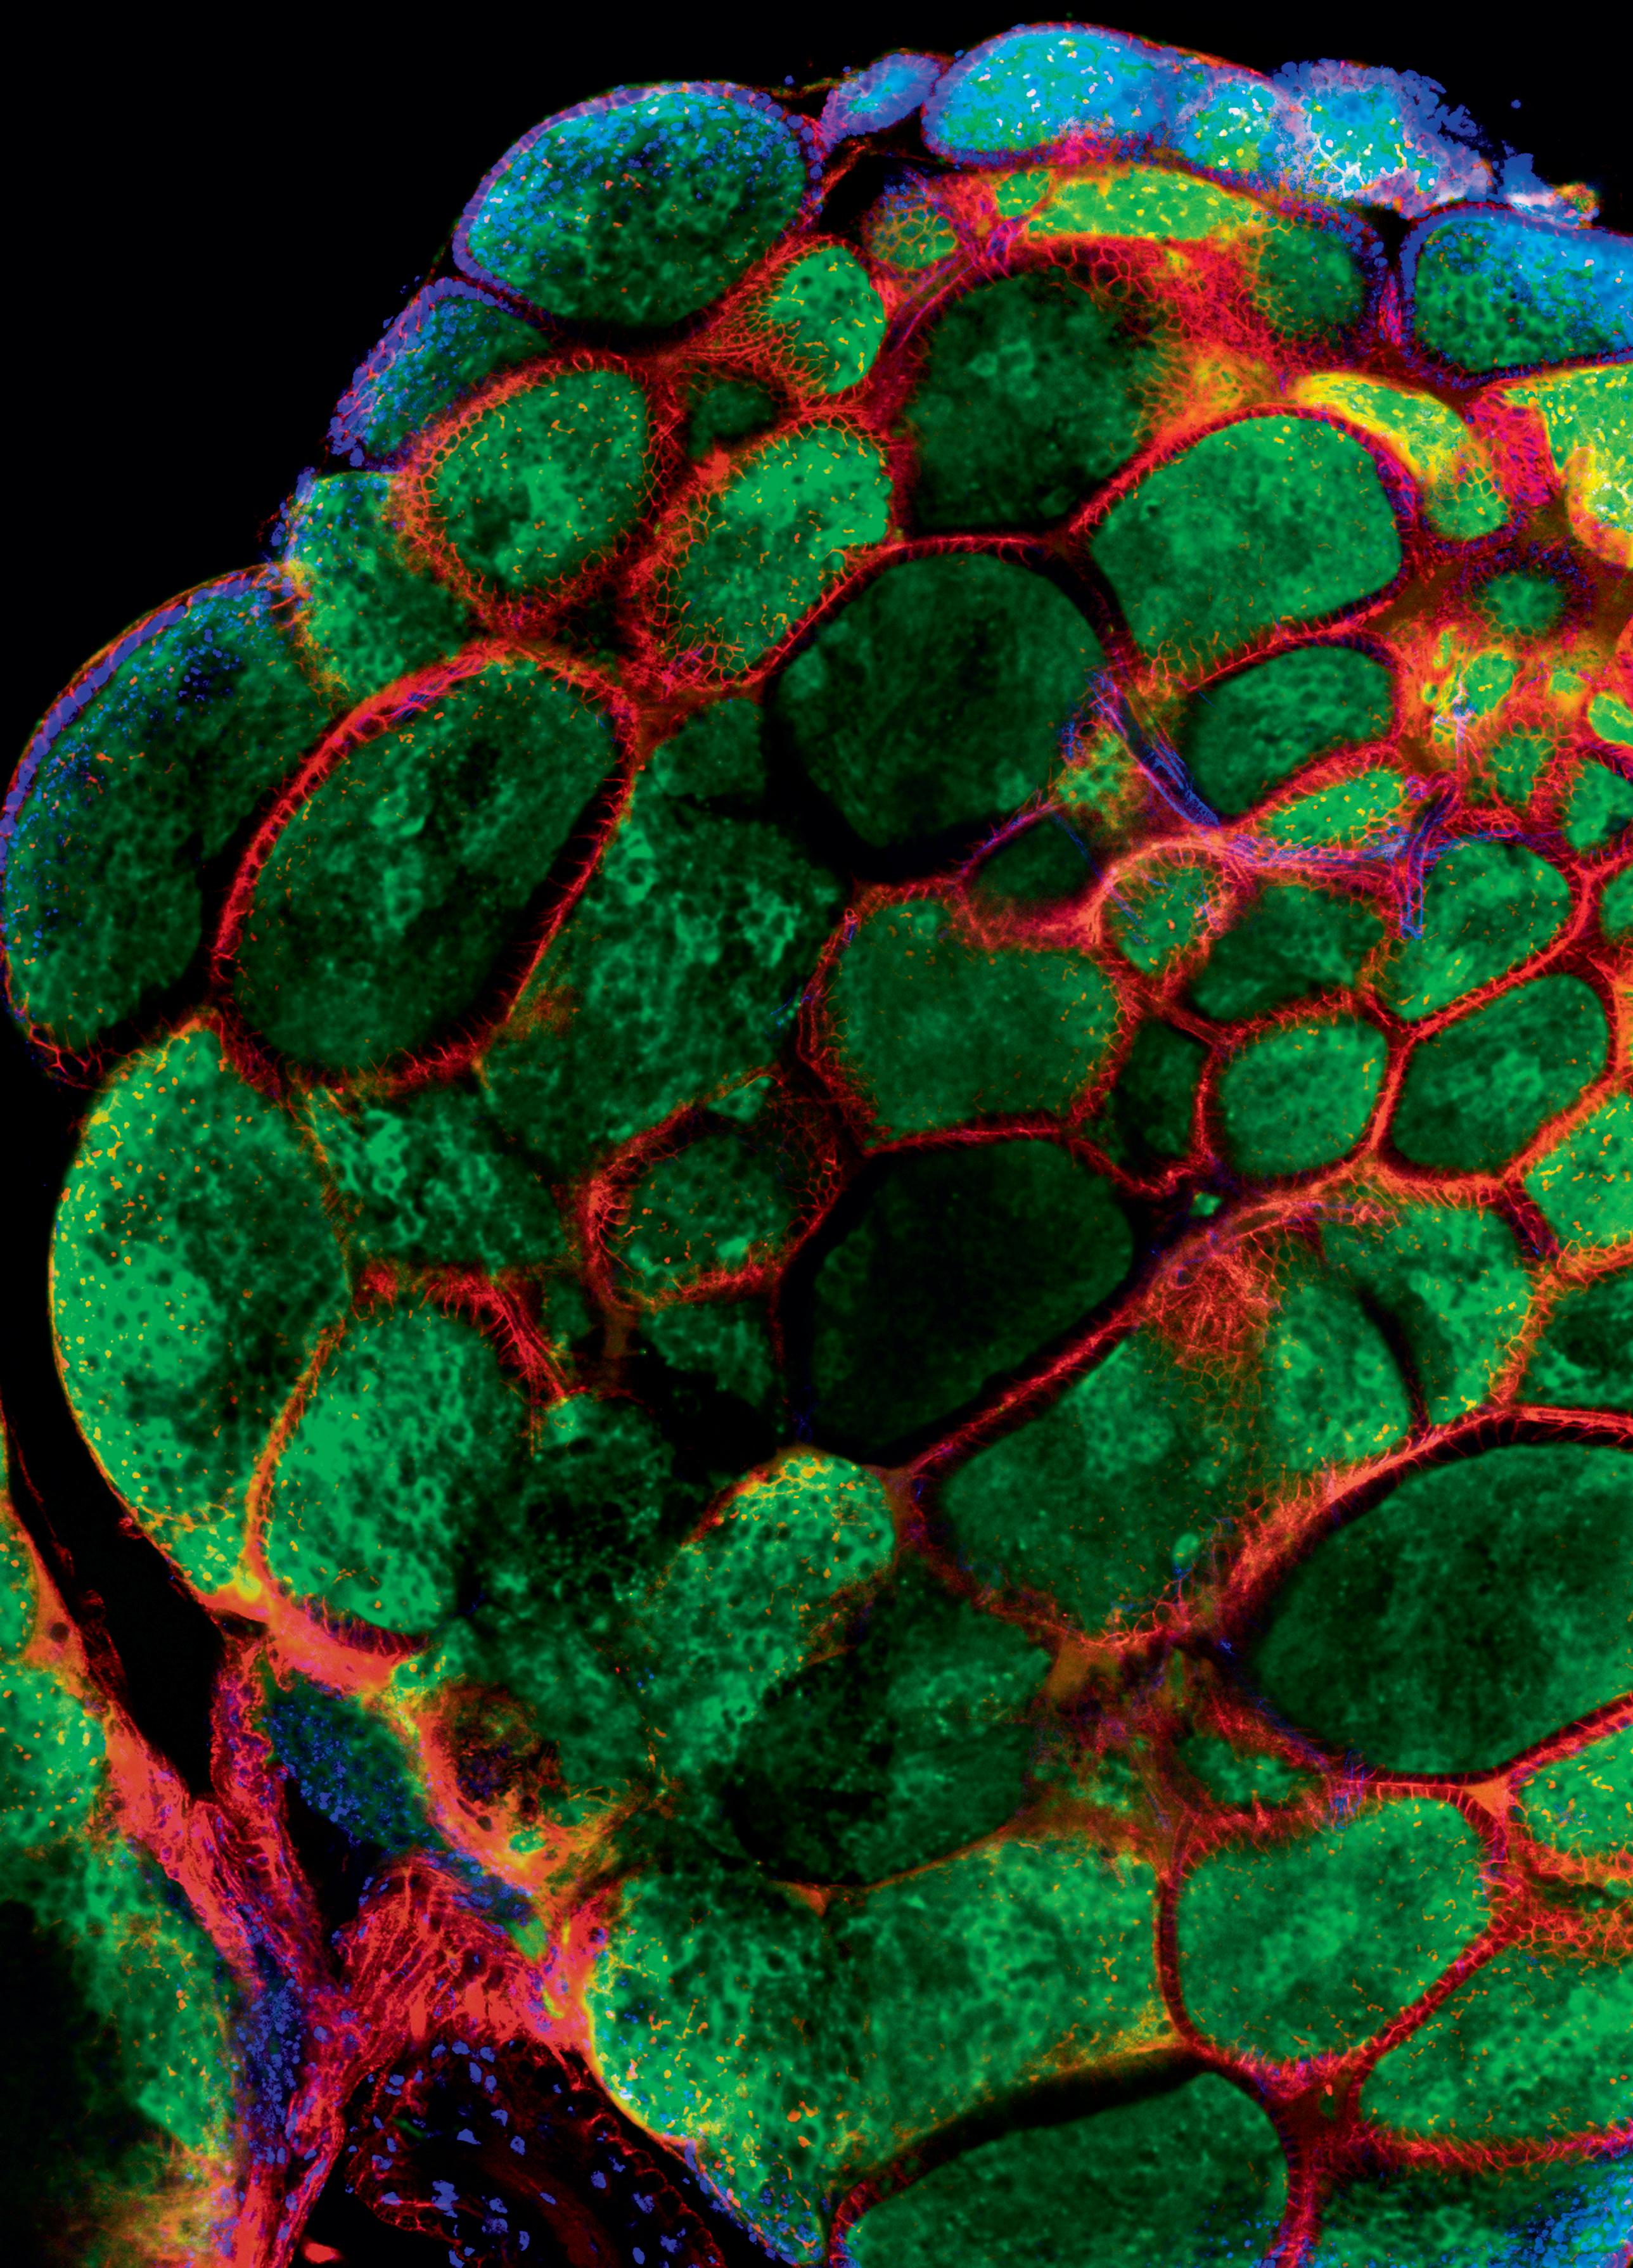

ass die Artenvielfalt in der Pflanzenwelt ein vielversprechendes Reservoir an potenziellen medizinischen stoffen bietet, konnten kürzlich deutsche Wissenschaftler untermauern. Sie untersuchten 26 Pflanzenarten aus dem Jemen und fanden anhand von Zellversuchen bei den meisten antioxidative und antimikrobielle Wirkungen oder einen positiven Einfluss auf das Wachstum von Krebszellen. ajo